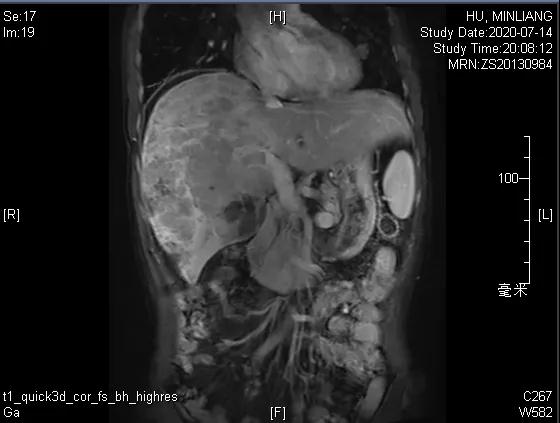

肝脏弹性超声:12kPa。腹部MRI平扫+增强:肝巨块结节性HCC(最大径18.4cm)伴肝内多发转移(最大径3.5cm),肝右静脉广泛癌栓形成;肝硬化伴门脉高压、脾大、少量腹水;肝囊肿;双肺多发转移。胸部CT平扫:两肺多发转移,两肺气肿伴肺大泡,两肺散在慢性炎症,右侧少量胸水。

Δ肝脏MRI,最大肿瘤18.4cm

肿瘤学评估(用药后2个月对比6个月):肝内主瘤明显缩小,动脉期强化降低;子灶消失;门脉右支癌栓明显缩小坏死;肺转移灶缩小,大部分消失。

Δ治疗过程中病灶影像学变化